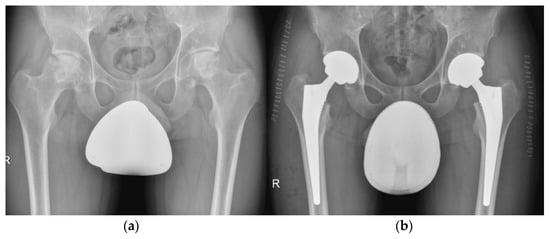

5.5. Hip

5.6. Knee